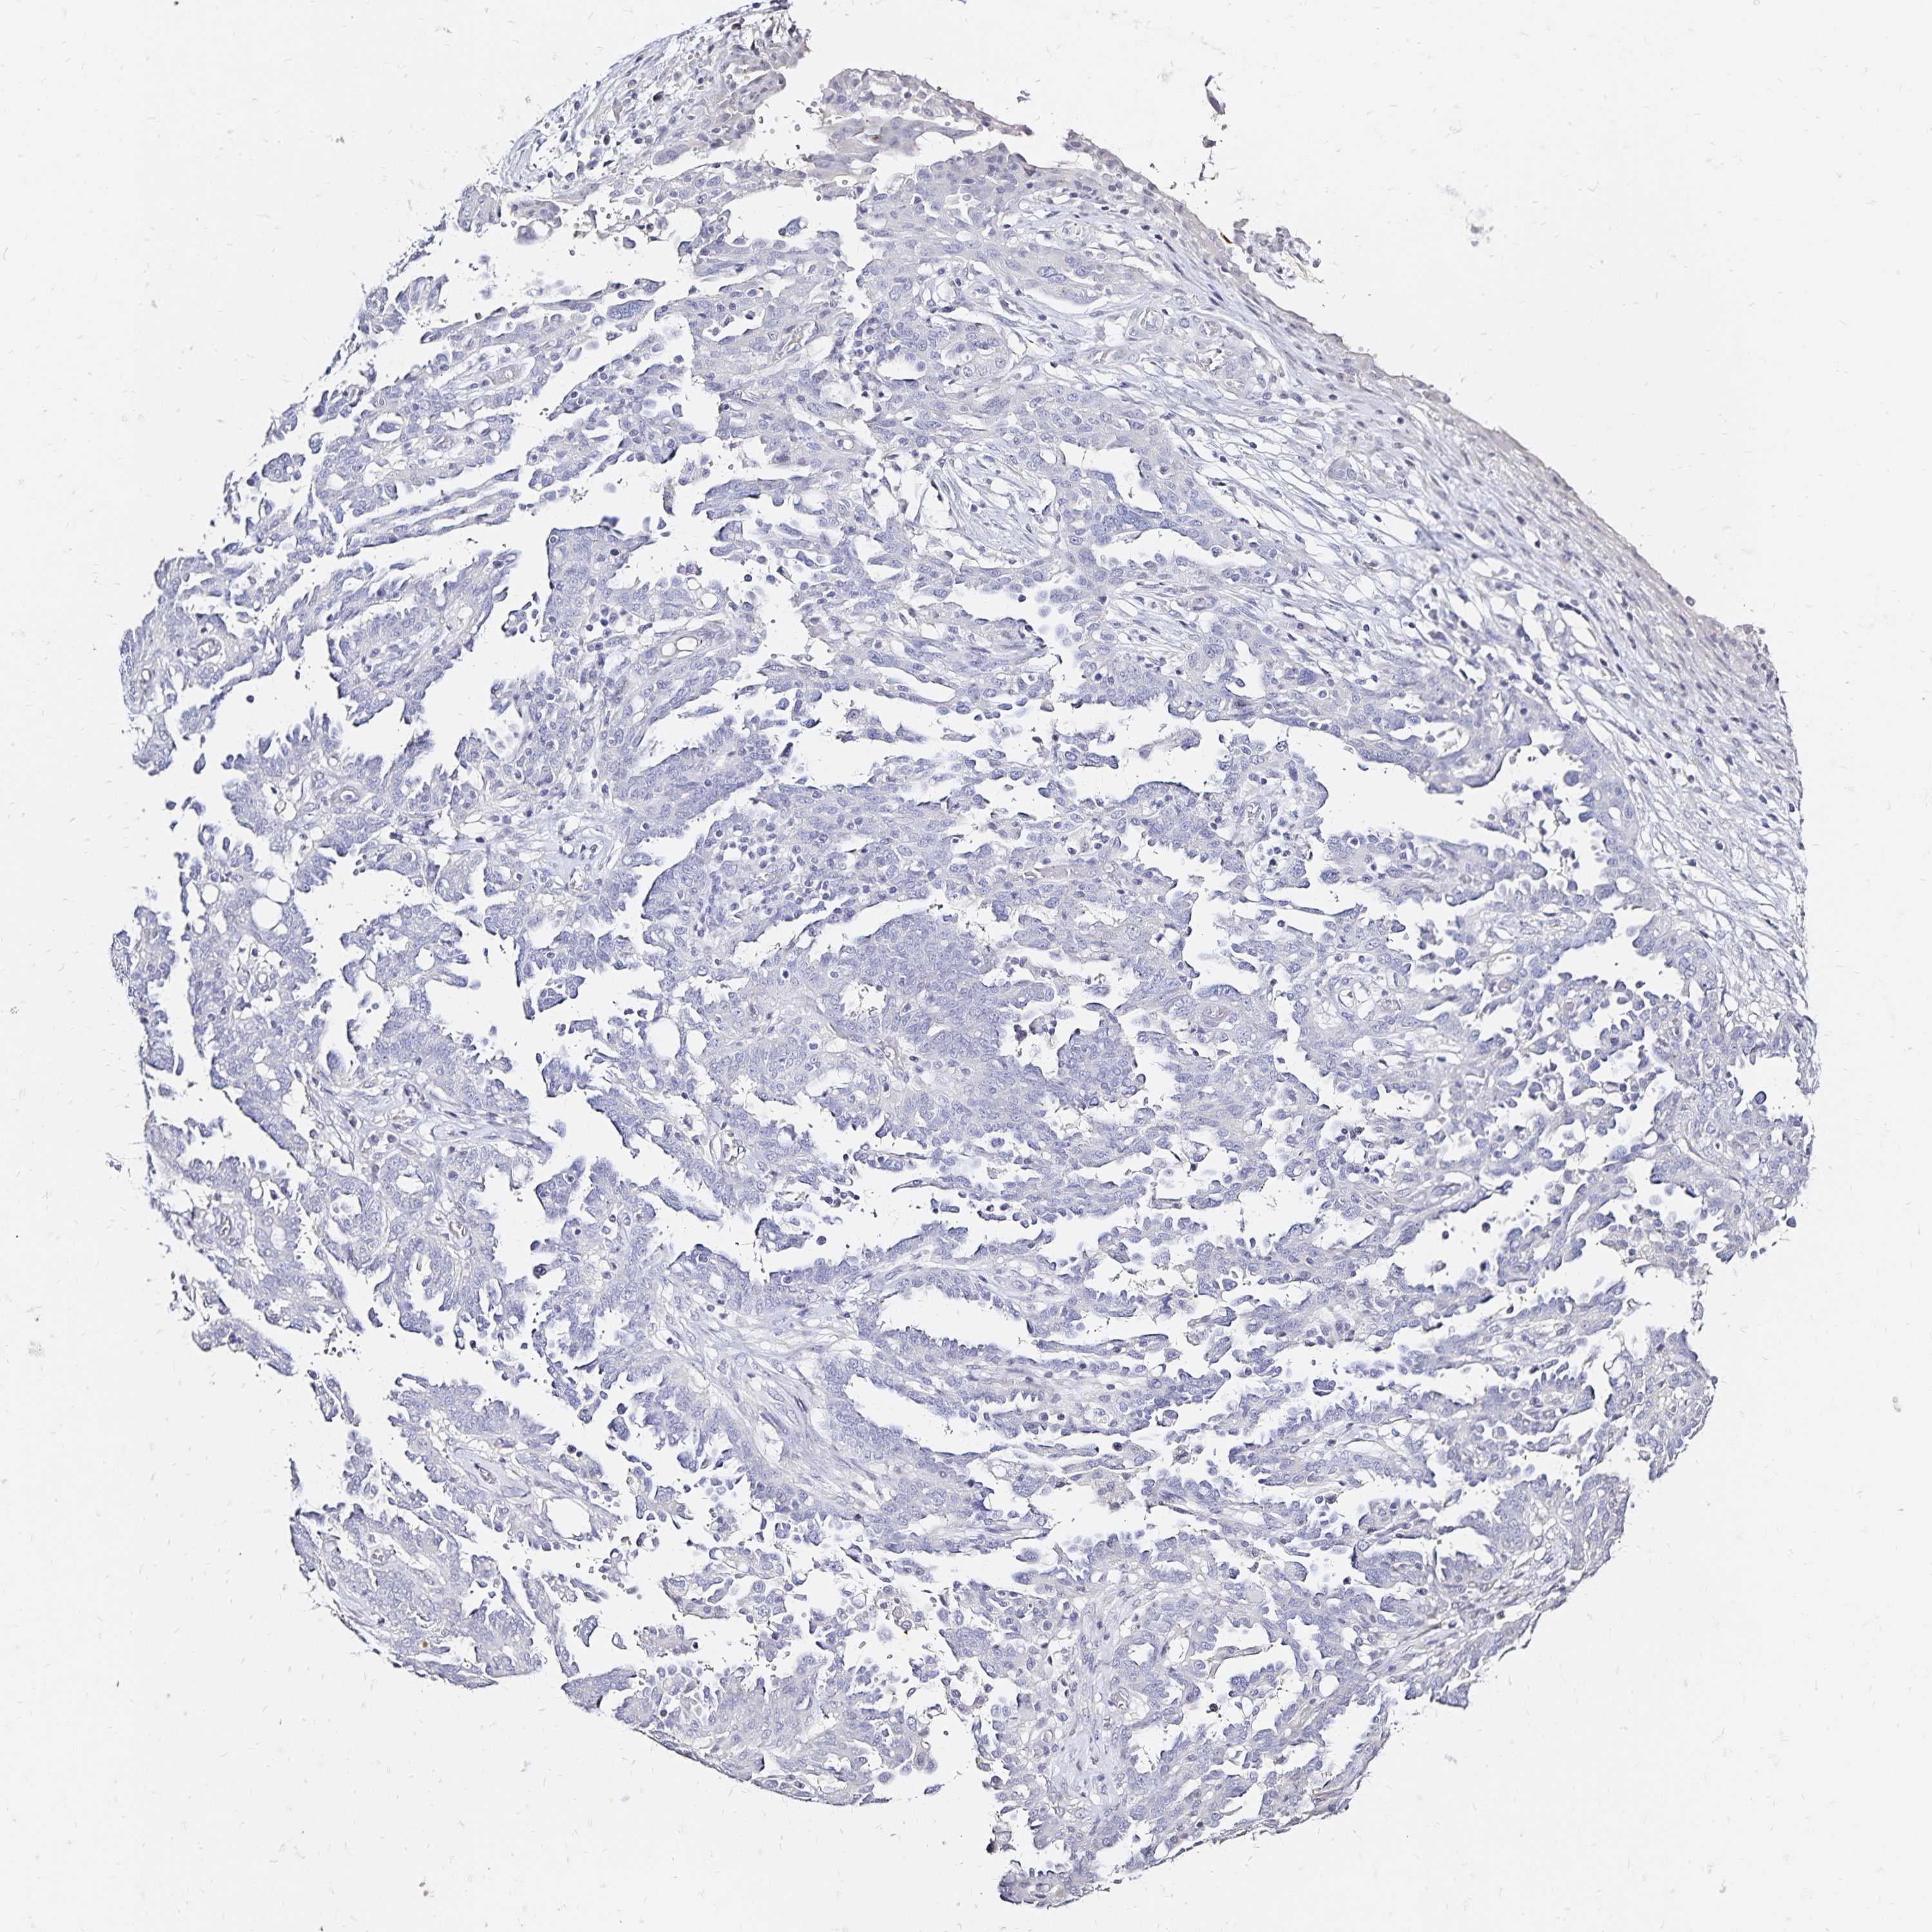

OVARIAN CANCER - Protein expressioni

A mouse-over function shows sample information and annotation data. Click on an image to view it in a full screen mode. Samples can be filtered based on level of antibody staining by selecting one or several of the following categories: high, medium, low and not detected. The assay and annotation is described here.

Note that samples used for immunohistochemistry by the Human Protein Atlas do not correspond to samples in the TCGA dataset.

Antibody stainingi

Antibody staining in the annotated cell types in the current human tissue is reported as not detected, low, medium, or high, based on conventional immunohistochemistry profiling in selected tissues. This score is based on the combination of the staining intensity and fraction of stained cells.

Each image is clickable and will lead to virtual microscopy that enables deeper exploration of all samples and also displays staining intensity scores, fraction scores and subcellular localization as well as patient and tissue information for each sample.

Antibody HPA051805

Antibody HPA055106

Antibody CAB015467

Staining

High

Medium

Low

Not detected

Intensity

Strong

Moderate

Weak

Negative

Quantity

>75%

75%-25%

<25%

None

Location

Nuclear

Cytoplasmic/membranous

Cytoplasmic/membranous,nuclear

Cystadenocarcinoma, serous, NOS

Cystadenocarcinoma, mucinous, NOS

Carcinoma, endometroid